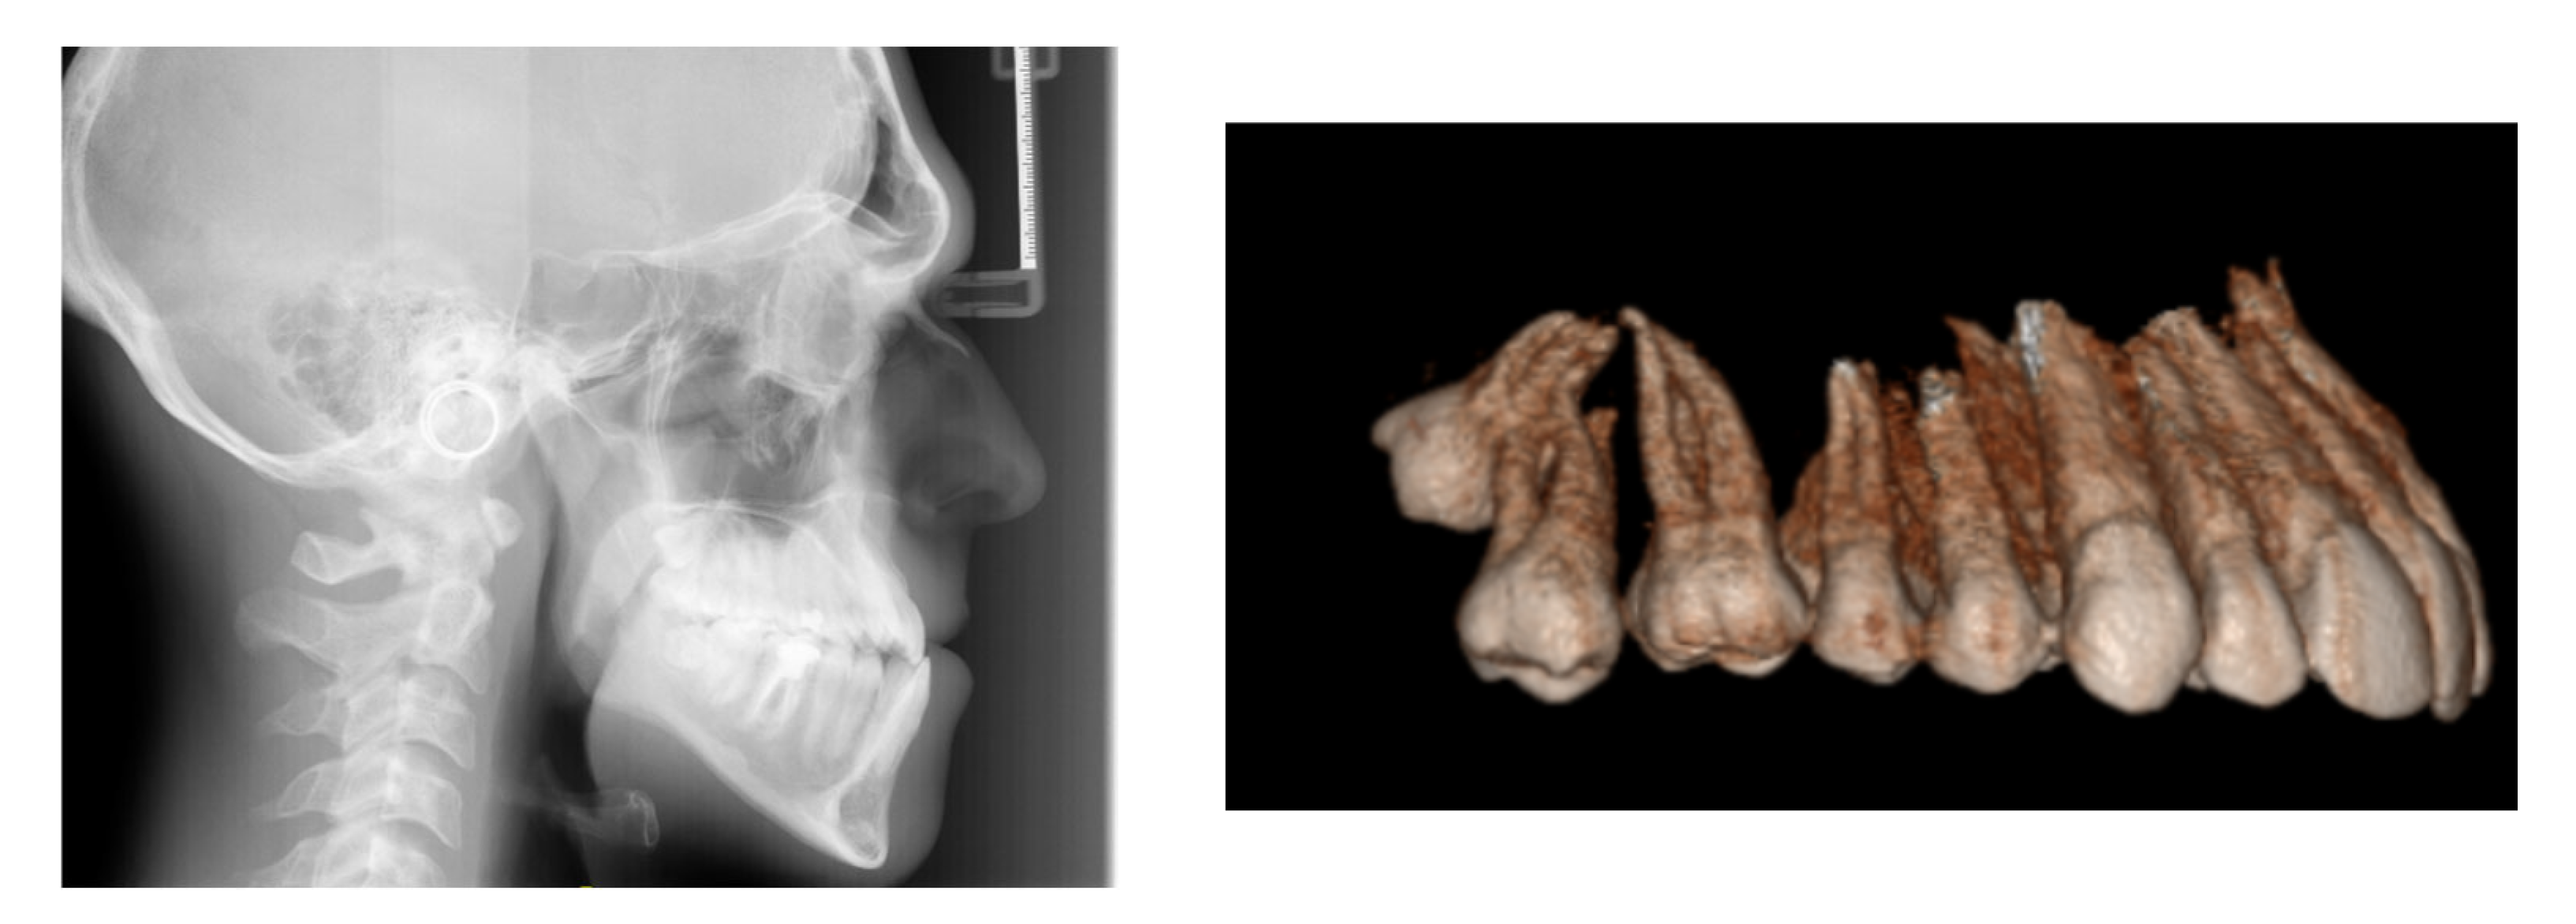

A 26-year-old male presented with a Class III malocclusion, having been repeatedly advised to undergo orthognathic surgery, which he categorically refused. Clinical examination revealed a bilateral full Class III molar relationship with anterior crossbite, reduced incisal overbite, particularly involving the lower left lateral incisor, which appeared in infraocclusion and marked extrusion of the upper right second molar, likely related to the full-step Class III malocclusion on the right and the absence of occlusal contact with the opposing lower right second molar. Transversely, mandibular endoalveolia suggested a compensatory adaptation to maxillary constriction. The lower incisors were retroclined, indicating dentoalveolar compensation of the crossbite. The facial profile was characteristic of a Class III pattern, with deficient malar projection and mandibular prominence, within a hyperdivergent skeletal context. Lingual posture was low and anterior at rest.

Cephalometric analysis confirmed a skeletal Class III relationship, with maxillary dentoalveolar protrusion and mandibular dentoalveolar retrusion. The patient exhibited a negative overjet and a minimal overbite. Given the patient’s refusal of surgical intervention, a dentoalveolar compensatory treatment plan was selected, aiming to correct the anterior crossbite and improve interarch relationships while maintaining vertical dimension control and addressing esthetic considerations.

Medical history was unremarkable, with no systemic diseases, drug allergies, or ongoing medications. No relevant family history of Class III malocclusion or significant maxillofacial dysmorphology was reported (Figure 1).

Figure 1. Initial records.